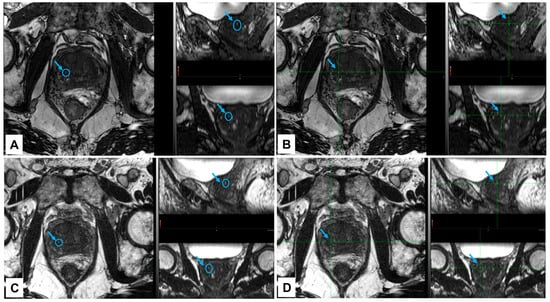

3.4. Visibility of NOVA Markers in a Clinical Case